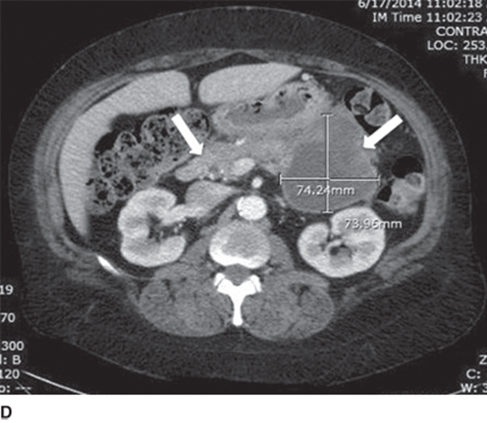

pancreatic adenocarcinoma. SMV abutted but not encased

pancreatic adenocarcinoma

normal on left